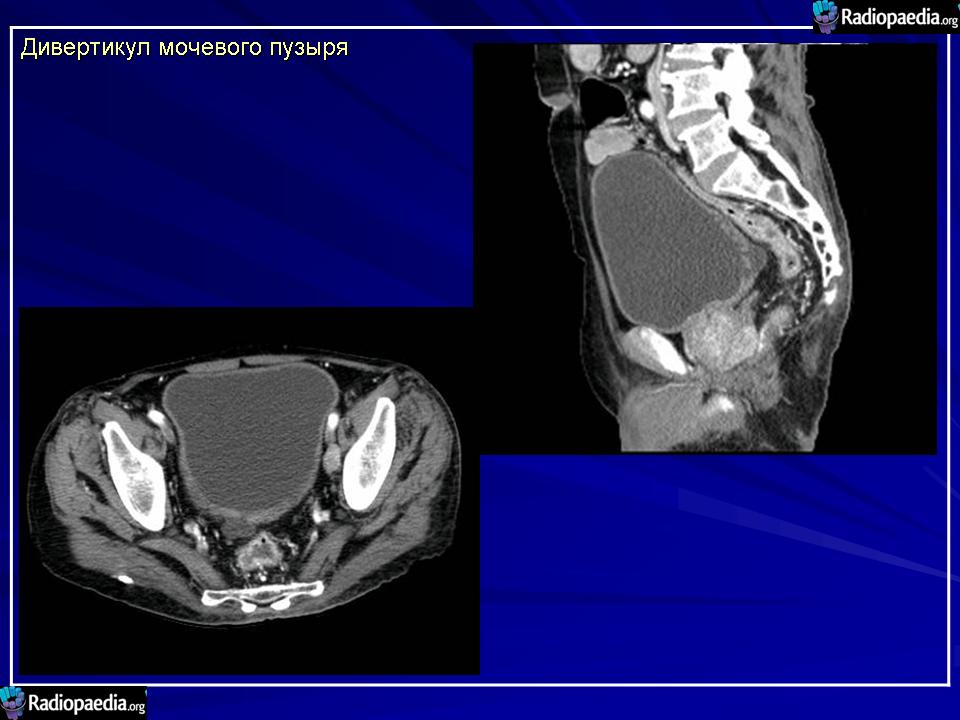

Дивертикулы мочевого пузыря.